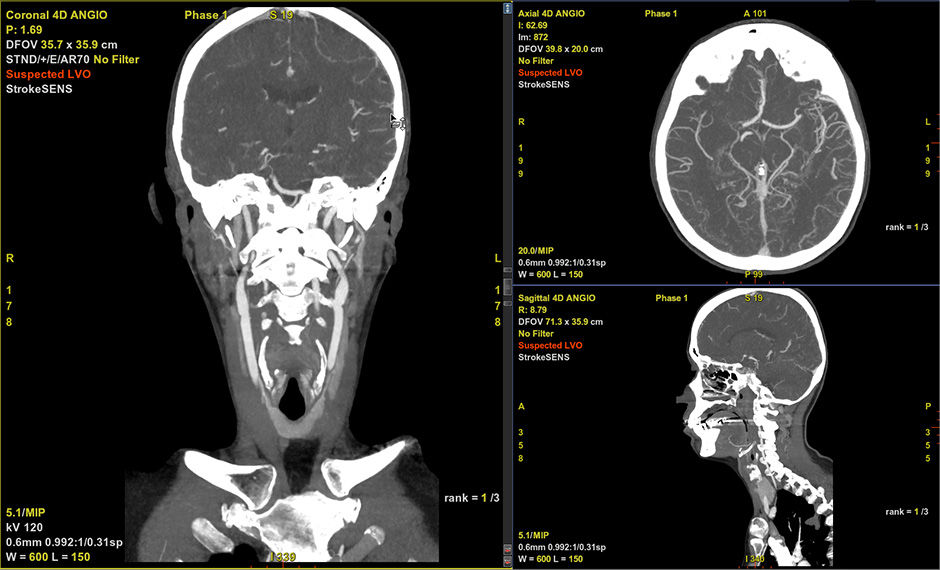

StrokeSENS LVO1

StrokeSENS LVO verwendet KI zur Erkennung von Verschlüssen großer Gefäße (LVO) in CT-Angiographien. StrokeSENS LVO benachrichtigt innerhalb von Minuten nach Erhalt des CTA-Bildes automatisch das Schlaganfallteam über vermutete LVO-Fälle und unterstützt so den frühzeitigen Einsatz des Schlaganfallteams. Wenn ein LVO erkannt wird, wird auf das DICOM-Eingabebild „Verdacht auf LVO“(CTA oder 1. Phase von MCTA) geschrieben, und die Ergebnisse werden automatisch in die E-Mail-Benachrichtigung aufgenommen, um das Schlaganfallteam über den zeitkritischen Fall zu informieren.

CT-Angiographie

Zeigt CTA-Bilder automatisch in einer dicken 2D-MIP-Ansicht mit optimierten WW/WL-Einstellungen an.

Umfasst die automatisierte LVO-Erkennung und -Meldung von StrokeSENS.1